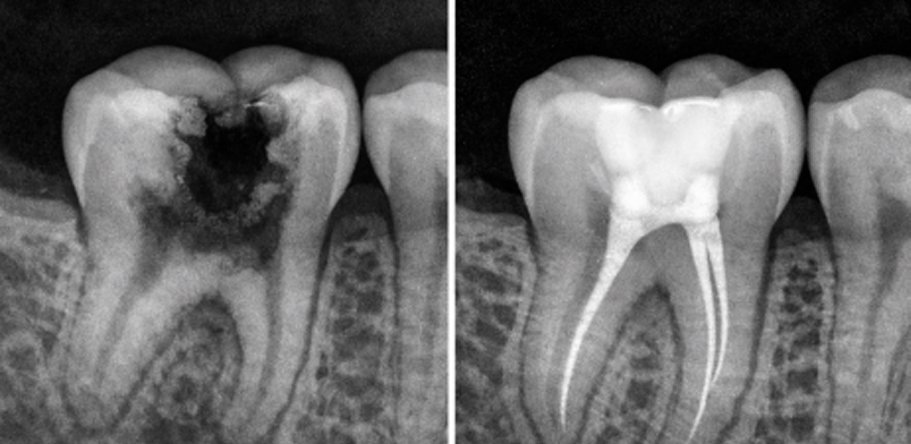

It’s a dental procedure designed to treat infections or damage inside a tooth. It involves removing the dental pulp (the soft tissue inside the tooth that contains nerves and blood vessels), followed by cleaning, disinfecting, and sealing the root canals. This treatment is recommended when the cavity is close to the nerve and is necessary when the pulp gets damaged or infected due to deep cavities. Its goal is to save the tooth and prevent it from being extracted.

Delaying treatment may lead to more costly and complex procedures, such as implants or bridges. This treatment is recommended when the cavity is close to the nerve and the tooth can still be saved from extraction.